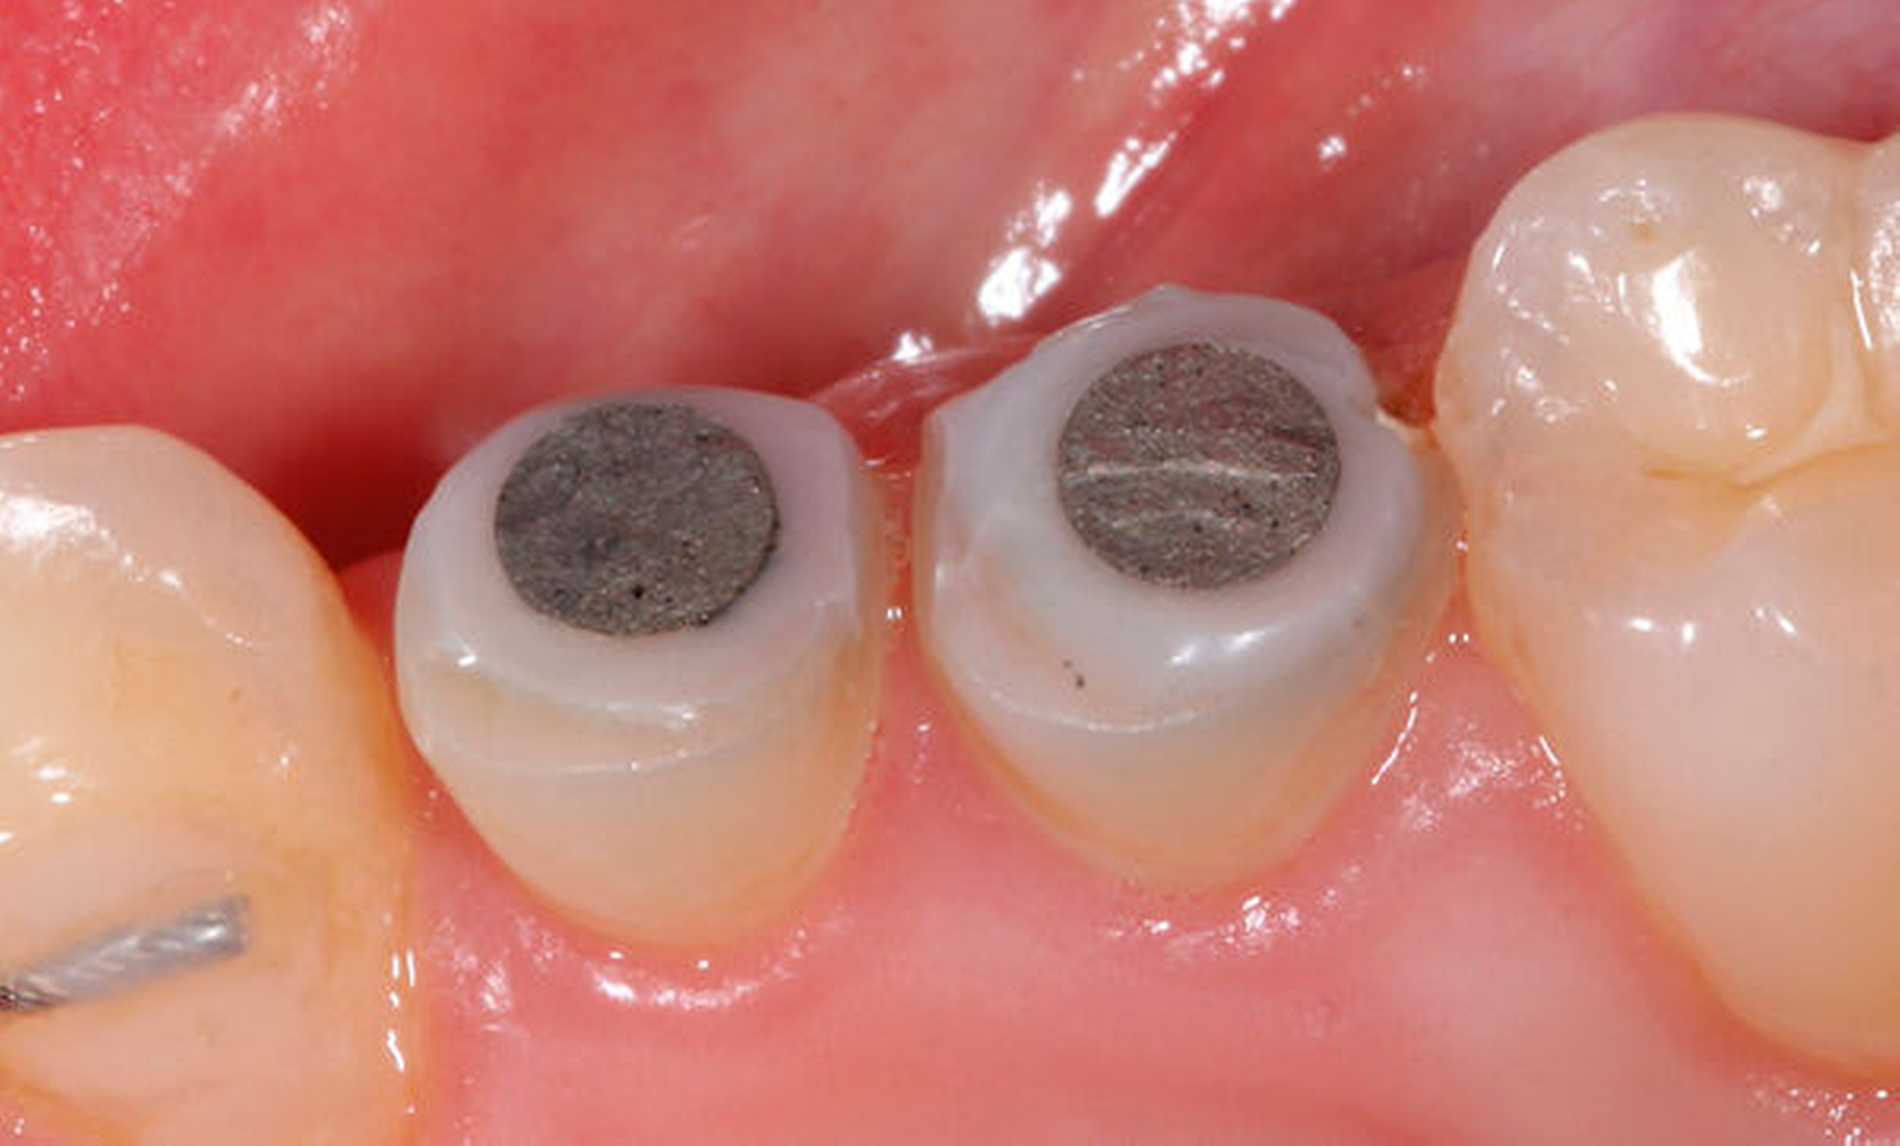

Als Hilfsmittel, die die Zugkräfte auf die betroffenen tief zerstörten Zähne übertragen können, eignen sich spezielle Magnet- oder Gummizug-Systeme (zum Beispiel Neodym-Scheibenmagnete; TMC Extrusion, Komet GmbH) (Abbildungen 12 und 13). Bei den Magnetsystemen ist in der Regel ein Abstand von 0,5 bis 2 mm zum Kontermagneten über einen Abstandshalter nötig. Der Kontermagnet wird in einer Tiefziehschiene oder in ein entsprechendes Methacrylatprovisorium mit Abstützung an den Nachbarzähnen einpolymerisiert. Die Zugkraft beeinflusst die Art der Extrusion. Kräfte mit circa 0,3 N verursachen eine verzögerte Extrusion um etwa 1 mm pro Woche. Die forcierte Extrusion erfordert mindestens 0,5 N, um eine Extrusion von mehr als 1 mm pro Woche zu bewirken [Krastl, 2004].